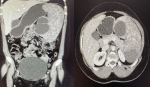

Computer tomography showed an enlarged spleen with multiple cystic lesions, varying in size, involving the entire spleen, replacing normal parenchyma (Figure 2), with the largest cysts measuring 8.8 x 5.1cm and 6.1 x 3.3cm, respectively. There were no associated peri-splenic fat stranding or collections suggesting an acute infectious process; no other pathological features were noted in the rest of the abdomen. Serological work-up for echinococcus and amoebiasis was negative, along with a negative human immunodeficiency virus test. Unfortunately, the imaging studies yielded no clear or definitive diagnosis; the need for tissue for histological assessment was evident, but proved to be challenging as to how such tissue would be obtained without subjecting the patient to unnecessary risks.

Figure 2: computed tomography abdominal views, left-coronal and right-transverse